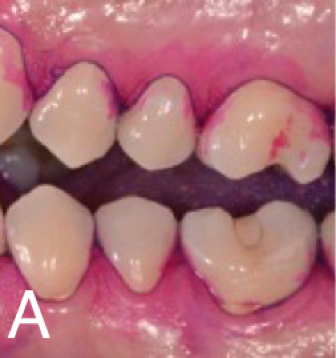

Clinically validated robot testing of plaque removal efficacy by manual and powered toothbrushes, computer-assisted plaque planimetry of 24 coronal fields and 6 root fields at four sites per tooth, including all tooth groups in the deciduous dentition, in mixed dentition and in the permanent dentition (see Publications).

Plaque is simulated either with our unique organic and anorganic plaque simulation giving superior discrimination of plaque removal efficacy for all different oral hygiene devices.